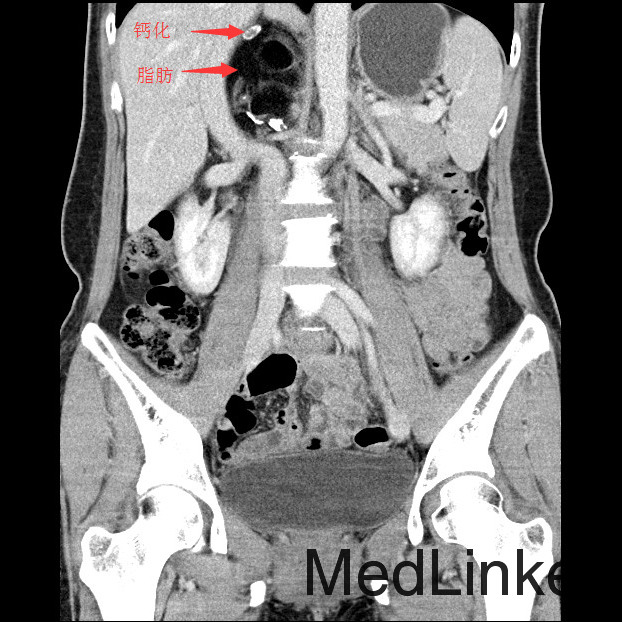

查体:神清,一般情况好,无水牛背、满月脸,皮肤无紫纹。 辅查:全腹CT平扫+增强提示右侧腹膜后区占位性病变,畸胎瘤可能性大。

讨论:本例畸胎瘤因发生在肾上腺区,因此表现为发作性高血压。一般只要在CT图像上看到钙化、脂肪密度等特征性征象,增强扫描实性成分轻度强化,畸胎瘤的诊断一般不难。不过非成熟性的畸胎瘤一般缺少钙化和脂肪成分,此时要与腹膜后其他来源的实性肿瘤相鉴别。本例病理大体能够看到毛发,也是畸胎瘤比较特征性的病理表现。